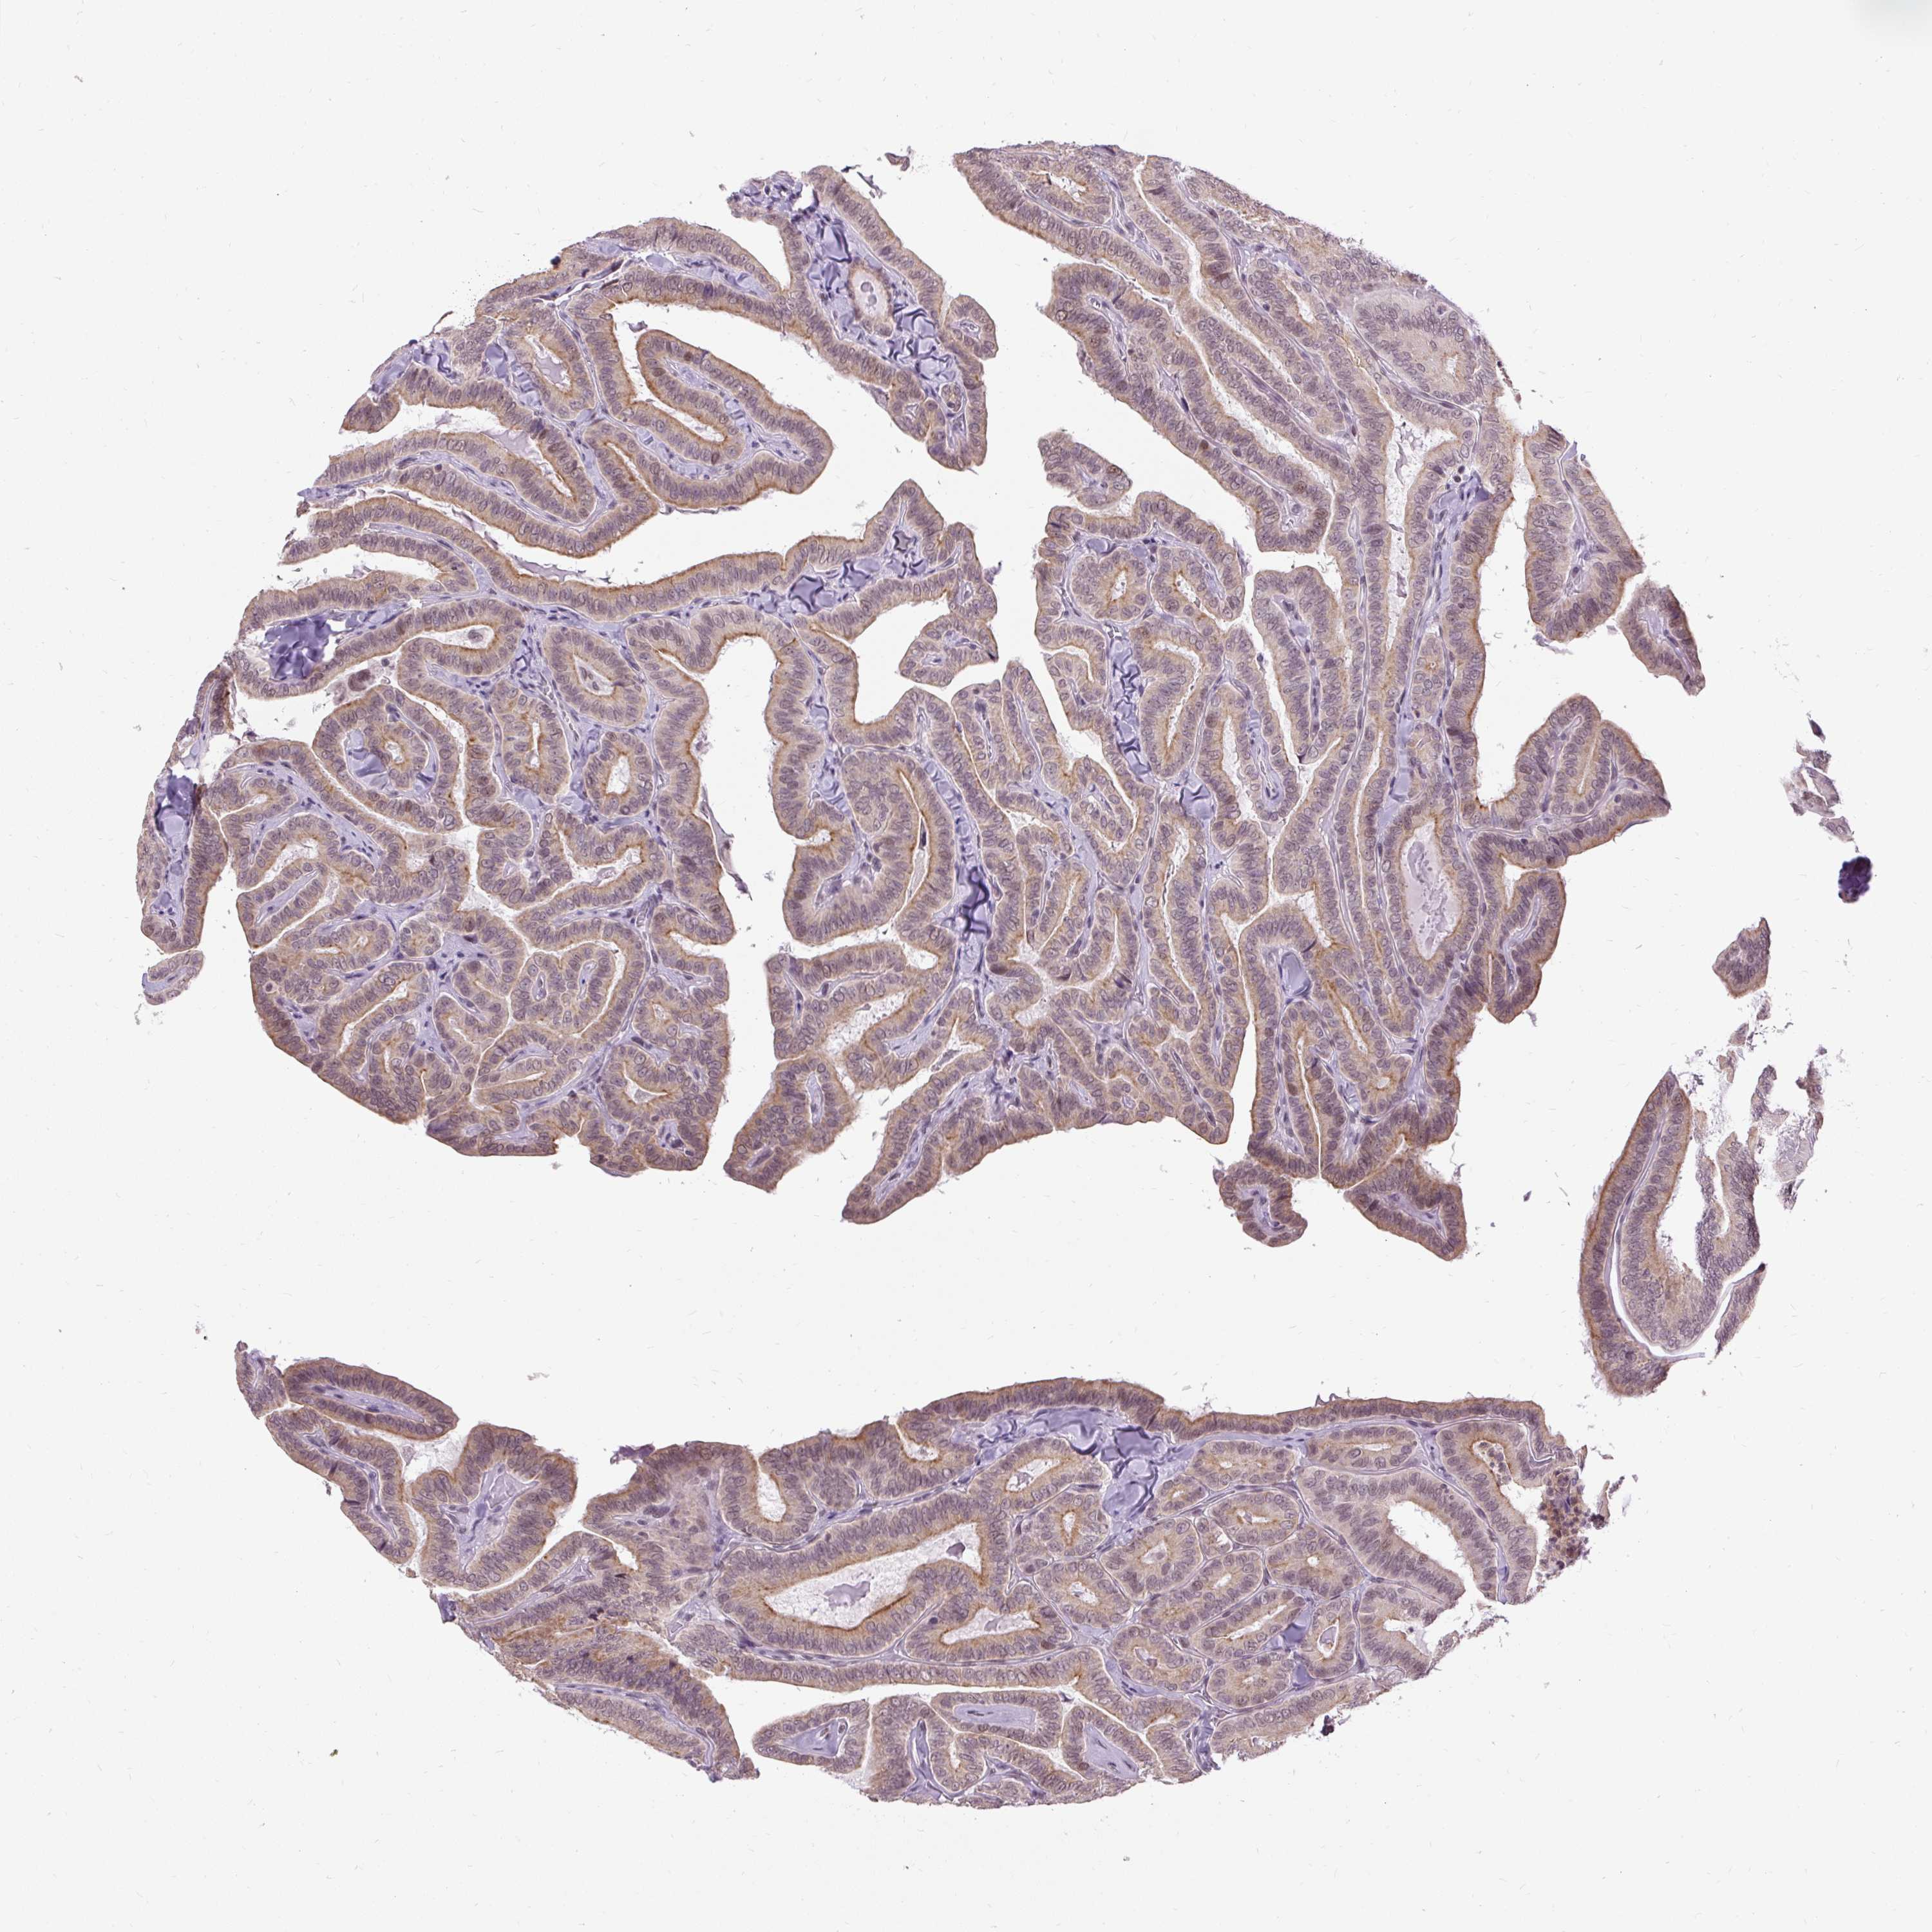

THYROID CANCER - Protein expressioni

A mouse-over function shows sample information and annotation data. Click on an image to view it in a full screen mode. Samples can be filtered based on level of antibody staining by selecting one or several of the following categories: high, medium, low and not detected. The assay and annotation is described here.

Note that samples used for immunohistochemistry by the Human Protein Atlas do not correspond to samples in the TCGA dataset.

Antibody stainingi

Antibody staining in the annotated cell types in the current human tissue is reported as not detected, low, medium, or high, based on conventional immunohistochemistry profiling in selected tissues. This score is based on the combination of the staining intensity and fraction of stained cells.

Each image is clickable and will lead to virtual microscopy that enables deeper exploration of all samples and also displays staining intensity scores, fraction scores and subcellular localization as well as patient and tissue information for each sample.

Antibody HPA055779

Staining

High

Medium

Low

Not detected

Intensity

Strong

Moderate

Weak

Negative

Quantity

>75%

75%-25%

<25%

None

Location

Nuclear

Cytoplasmic/membranous

Cytoplasmic/membranous,nuclear

Papillary adenocarcinoma, NOS

Follicular adenoma carcinoma, NOS